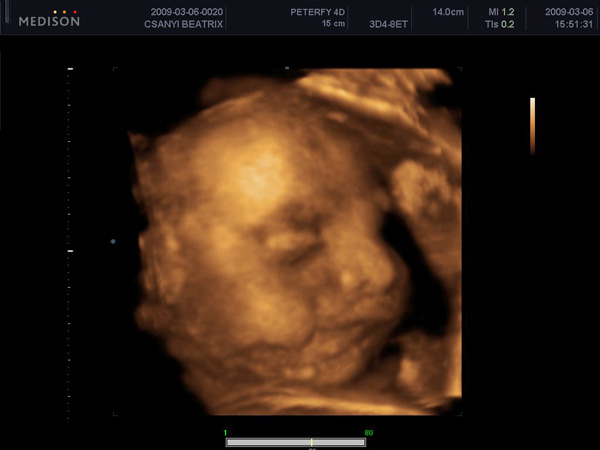

trixi nagyon édes kicsi fiad az uh. képen :)